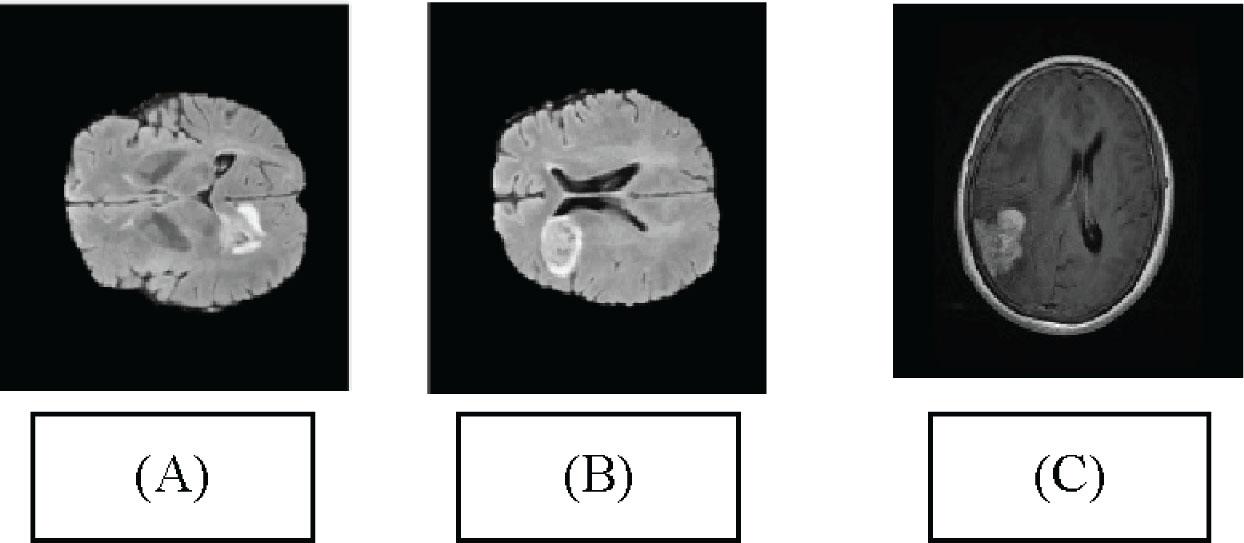

Illustration (A) Segmented image for the T1 MRI image (B) Segmented image for the T2 MRI image. (C) Segmented image for the FLAIR MRI image. MRI, magnetic resonance imaging.